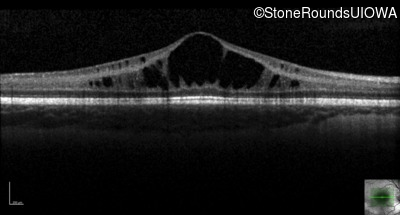

XL Retinoschisis (IIIB1)

XL Retinoschisis (IIIB1)

This 6 year old boy first experienced difficulty reading and seeing the blackboard at age 5.